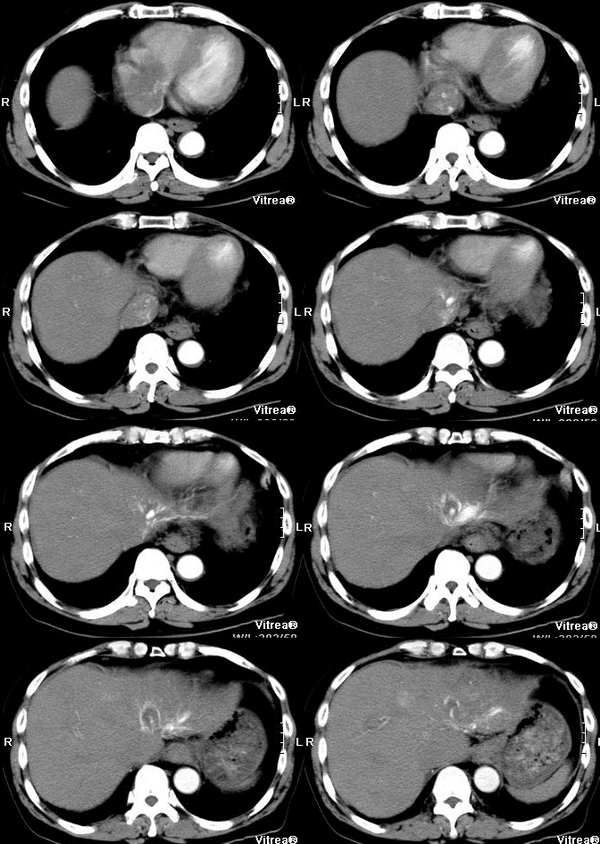

男性,58岁,肝硬化数年,近几个月出现黄疸,腹胀,食欲下降,尤其双下肢浮肿明显。超声提示肝脏多个结节。ct三期扫描图像如下:

动脉期:

肝左叶不规则肿块,血供不丰富,早期强化不明显,三期符合肝癌块尽快出的特点。门静脉、腔静脉近右房段增粗,早期见癌栓滋养血管强化明显。

肝静脉:在动脉期的第一张图片上就可以看到右心房的充盈缺损和下腔静脉近心段的明显增粗,增粗的下腔静脉内部可以见到点状、条状的强化血管影,这些强化的血管影是什么来源?这些高密度影蜿蜒曲折,和主动脉同时显影,所以只能考虑为主动脉的分支血管之一。到门脉期和平衡期,右心房的充盈缺损更加明显了,肝静脉和下腔静脉的强化非常微弱,肝段下腔静脉的管腔十分狭窄,但肝外段的下腔静脉明显的饱满,这是由于右心房的充盈缺损和下腔静脉近心段的栓子梗阻造成的。在动脉期肝左叶有一条横行血管也非常引人注目,考虑为肝左静脉的可能,但其汇入腔静脉端呈一盲端,估计终止于栓子部位,该血管的过早显影提示存在动静脉分流,从病因上来说以原发性肝癌最为常见。在临床上,该患者有双下肢明显的浮肿,要用下腔静脉的梗阻来解释。

门静脉:门静脉不论在门静脉期还是实质期(其实对于这个病人来说,我们平常所说的门静脉期还是实质期已经不适用了)均未见显影,在实质期反而发现门静脉和周围密度增高的肝实质相比呈低密度,这说明门静脉主干和主要分支均形成栓子。由于正常情况下,肝脏的大部分血供来自门静脉,这就造成了肝脏的强化幅度明显下降。在胰头勾突前方可以见到扩张的血管分支,应该为门静脉的侧枝循环血管,但是奇怪的一点是脾脏不大,不太好解释。

肝动脉:从动脉期看,肝门区肝动脉及其分支明显的增粗、增多。非常值得注意的是肝左叶见到明显扩张的肝动脉分支,这是动脉期估计肿瘤部位的重要线索。

肿瘤:由于肝脏本身存在血液循环的异常,所以肿瘤的血供也会受到影响。该患者在动脉期肝左叶见到明显扩张的肝动脉分支和肝左静脉的早期显影,强烈提示左叶病变。尽管没有见到明显的动脉期肿瘤强化,但仔细观察还是有动脉供血病变的,不过密度较淡,边缘模糊;在平衡期,左叶肿瘤露出其真面目,和肝脏实质相比呈低密度。由于患者有多年肝硬化病史和存在动静脉分流和静脉栓子,综合考虑还是应该首先考虑为原发性肝癌。另外腔静脉内栓子动脉期明显动脉供血,也是肝癌癌栓的特征,这一点和hejie的意见不同。

肝脏超声提示多发占位,仔细观察动脉期在肝脏左右叶交界和肝右叶后段均可以见到小片状强化,尽管不很典型也应该考虑为癌瘤,由于肝脏多发的癌瘤,造成了门静脉、肝静脉系的广泛癌栓。